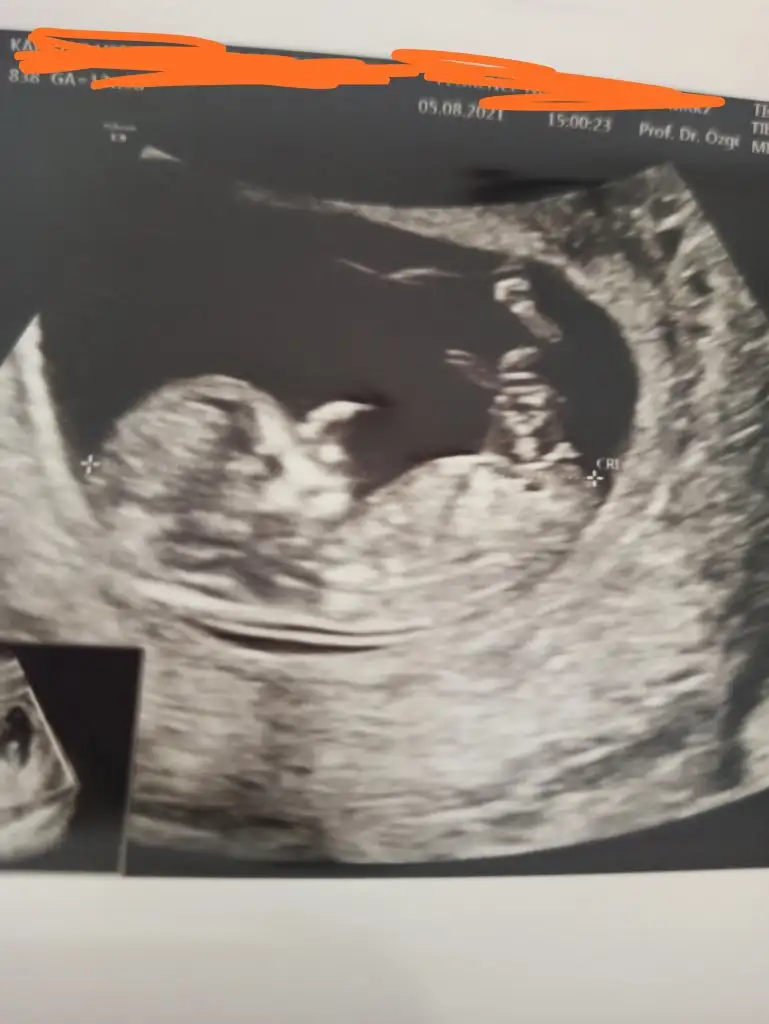

Emin olamadım kız sankiEki Görüntüle 2896743 cinsiyetini çok merak ediyorum bakabilirmisiniz

Erkek gibi sanki emin olamadım en iyi 11 12 13 haftalarEki Görüntüle 2896935 merhabalar tahmininizi alabilir miyim. SAT a göre 13+1 usg de 14 çıktı

Erkek sanki emin olamadımIkra meyra İki farklı doktor kız dedi bugün 16 haftalık bacak arası fotosu dr erkek olduğu nu söyledi o bacak arasındaki pipimi doktor öyle dedi sizin de fikrinizi alabilir miyim

Erkek sanki emin olamadım